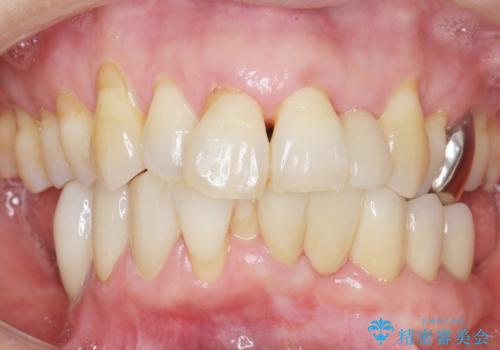

気にされていた前歯と奥歯の動揺がなくなったことと自然な仕上がりに喜んで頂けました。

クラウンの種類:オールセラミッククラウン スタンダード